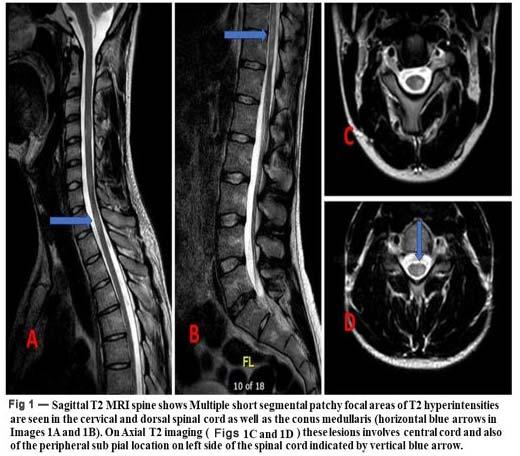

Routine blood investigations, ECG, chest Xray, CT scan and MRI of the face (including orbits) and brain were done (Fig 1).

Fig 1 — Pre-operative and Postoperative coronal MRI slice

In India till May 2020, 66.8% of the COVID-19 cases were males19. Rhino-cerebro-orbital (44-49%) was the type most commonly found, followed by cutaneous (10-19%), pulmonary (10-11%), disseminated (6-11%) and gastrointestinal (2-11%)20. But in our case study, all the cases occurring with COVID-19, diabetes and steroids led to rhino-cerebro-orbital mucormycosis. Patients usually presented with headache, fever, unilateral facial swelling, orbital cellulitis with the presence of palpebral oedema, chemosis, ptosis and ophthalmoplegia21. The prognosis is poor with about 33.3%-80% being the overall mortality rate21,22. CT scan is usually the first diagnostic tool to check the status of sinuses, although best way to detect extrasinus spread is using Magnetic Resonance Imaging (MRI)9. A definitive diagnosis of mucormycosis as the causative species is achieved only by histological examination of the biopsy specimen. Culture and KOH examination may be used only as a suggestive tool for noting the presence of mucormycosis.